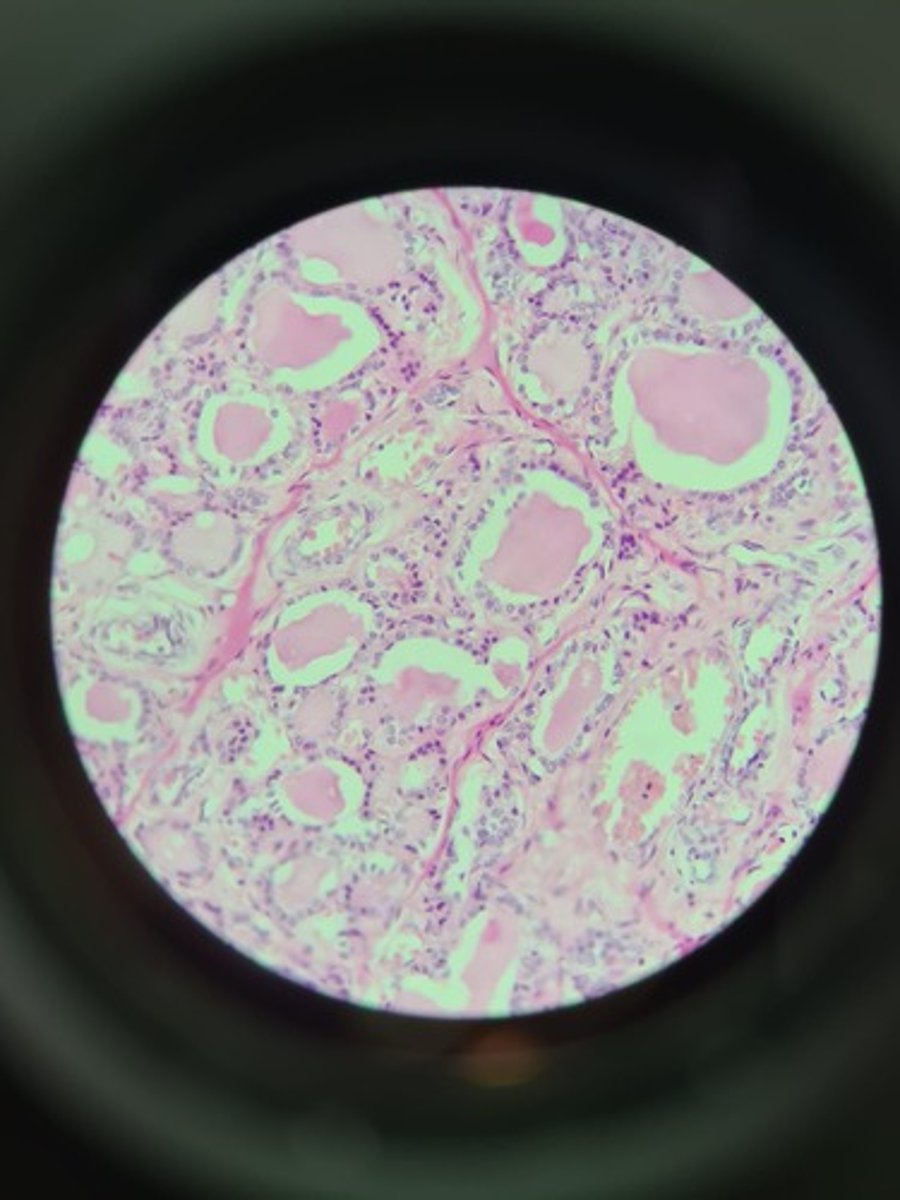

Thyroid gland HE

Thyroid gland HE

Thyroid gland HE

Thyroid HE

Thyroid HE